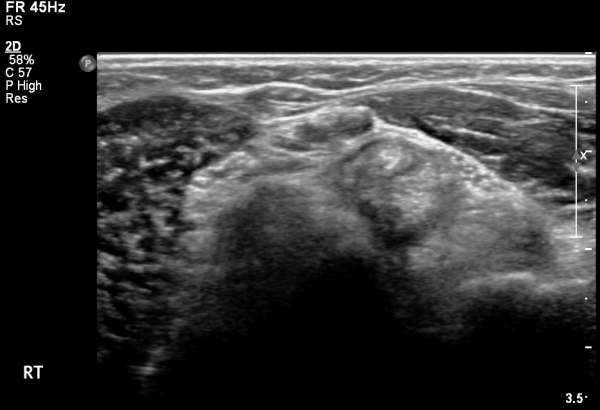

ÆÈ²ÞÄ¡ ¾Õ ÀÌµÎ¹Ú±Ù°Ç È¸´Ü¸ç°Ë»ç¿¡¼­ ÀÌµÎ¹Ú±Ù°Ç ¿ÜÃø¿¡ ¼ö¾×Àú·ù°¡ °üÂûµÊ(»çÁø 1).